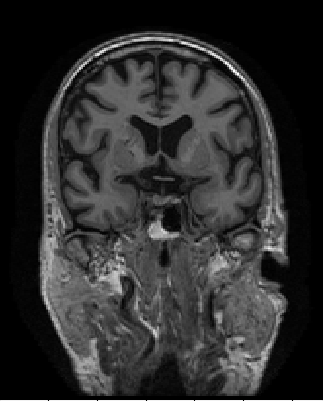

(a) The axial, coronal, and sagittal view of the “preprocessed” scans.

(b) The axial, coronal, and sagittal view of the FreeSurfer post-processed scans.